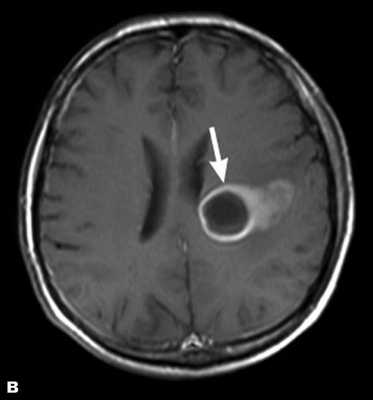

Злокачественная опухоль на МРТ

Злокачественные опухоли характеризуются инвазивностью, то есть врастанием в здоровые ткани, поэтому контуры таких образований нечеткие и неровные, а потому достоверно определять границы таких опухолей довольно сложно. Кроме того, структура злокачественной опухоли часто бывает неоднородна за счет распада (некроза), кровоизлияния и коллоидной дегенерации. Вокруг злокачественной опухоли, как правило, выявляется выраженный перифокальный отек, который может приводить к смещению срединных структур головного мозга и появлению аксиальной дислокации. Также могут быть выявлены признаки метастазирования.